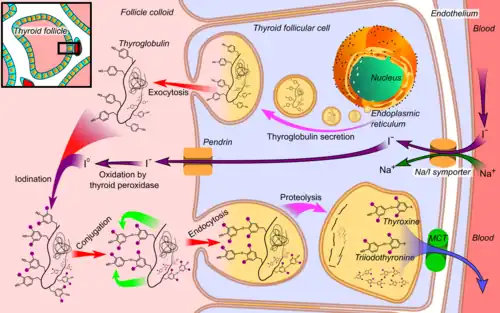

Produção de hormônios

Os hormônios da tireoide são criados a partir da tireoglobulina. Esta é uma proteína dentro do colóide no lúmen folicular que é originalmente criada dentro do retículo endoplasmático rugoso das células foliculares e então transportada para o lúmen folicular. A tireoglobulina contém 123 unidades de tirosina, que reage com o iodo no lúmen folicular.[33]

O iodo é essencial para a produção dos hormônios da tireoide. O iodo (I0) viaja no sangue como iodeto (I−), que é absorvido pelas células foliculares por um simportador de iodeto de sódio. Este é um canal iônico na membrana celular que, na mesma ação, transporta dois íons sódio e um íon iodeto para dentro da célula.[34] O iodeto então viaja de dentro da célula para o lúmen, através da ação da pendrina, um antiporter iodeto-cloreto. No lúmen folicular, o iodeto é então oxidado a iodo. Isso o torna mais reativo,[35] e o iodo é ligado às unidades ativas de tirosina na tireoglobulina pela enzima peroxidase tireoidiana. Isso forma os precursores dos hormônios tireoidianos monoiodotirosina (MIT) e diiodotirosina (DIT).[2]

Quando as células foliculares são estimuladas pelo hormônio estimulador da tireoide, as células foliculares reabsorvem a tireoglobulina do lúmen folicular. As tirosinas iodadas são clivadas, formando os hormônios tireoidianos T4, T3, DIT, MIT e traços de triiodotironina reversa. T3 e T4 são liberados no sangue. Os hormônios secretados pela glândula são cerca de 80–90% T4 e cerca de 10–20% T3.[36][37] As enzimas deiodinase nos tecidos periféricos removem o iodo do MIT e DIT e convertem T4 em T3 e RT3.[33] Esta é a principal fonte de RT3 (95%) e T3 (87%) nos tecidos periféricos.[38]